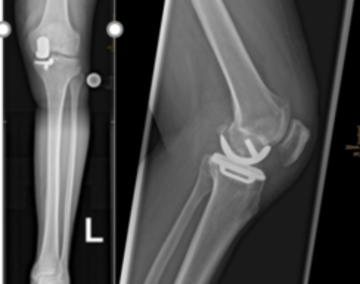

Schlittenprothese (unicondylärer Gelenkersatz, Teilgelenkersatz, Monoschlitten)

Wenn nur der äußere oder innere Anteil des Kniegelenkes betroffen ist, besteht die Möglichkeit diesen Teil des Gelenkes mit einer Schlittenprothese zu versorgen.